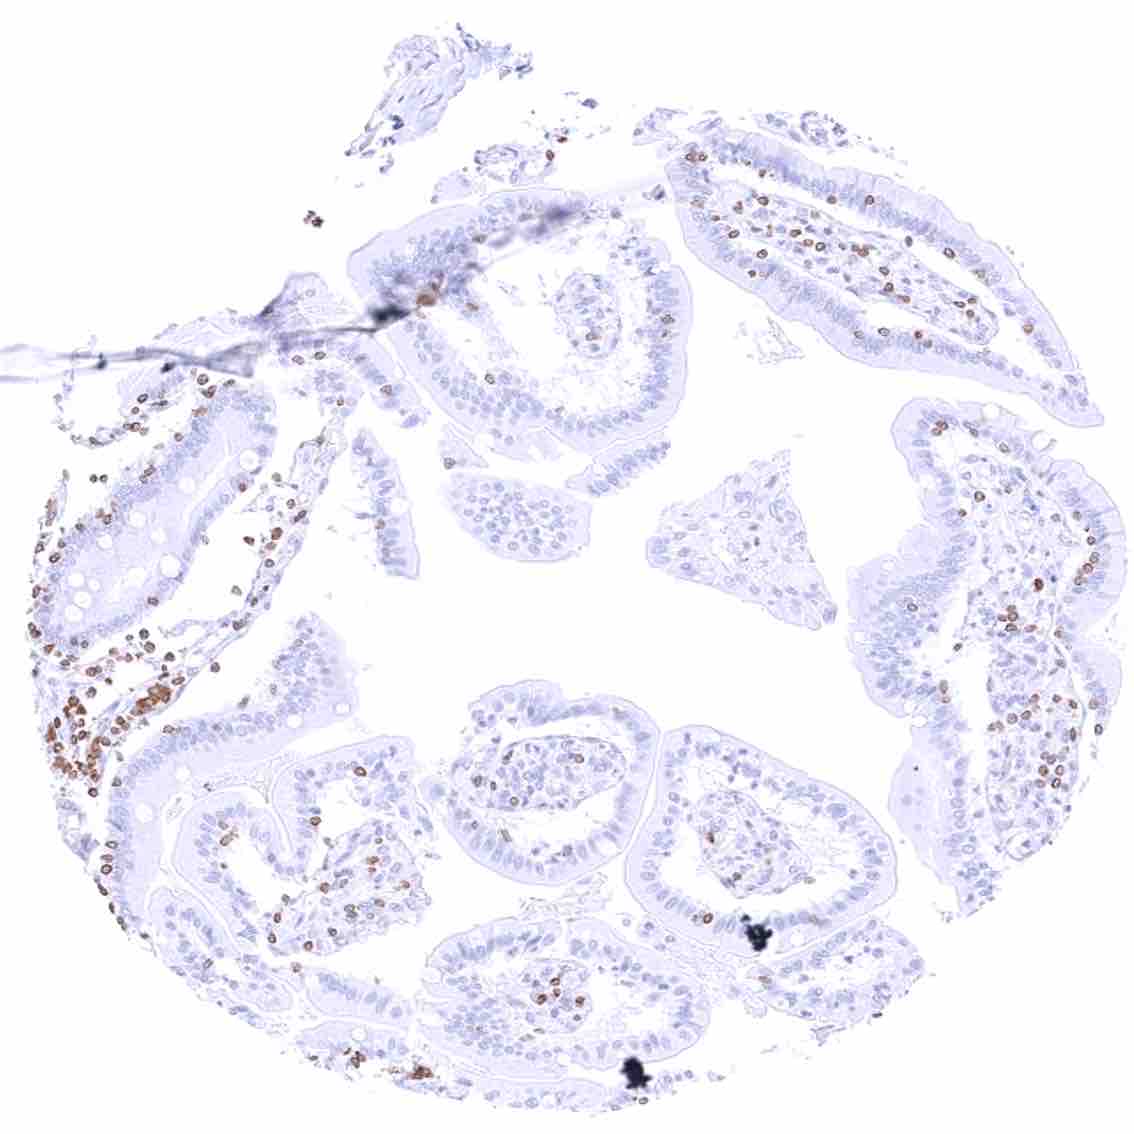

Duodenum, mucosa – Cytoplasmic bcl-2 staining is largely limited to lymphocytes. The epithelium is mostly negative, but a weak staining occurs in some crypt cells.